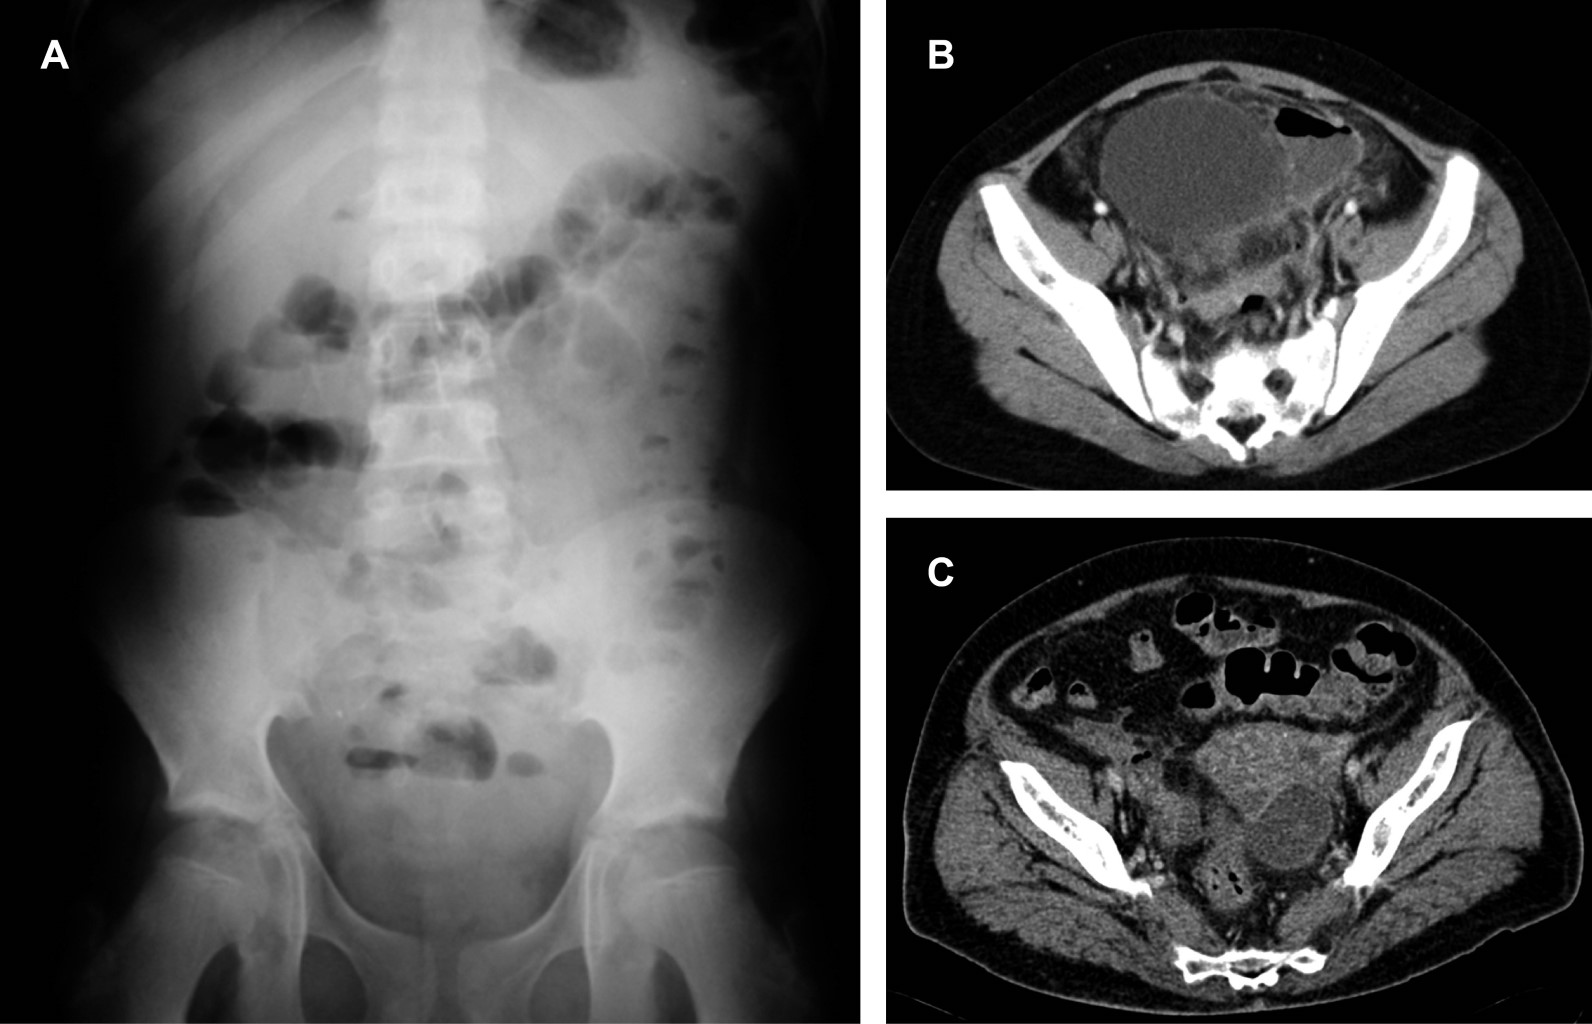

APARIENCIA POR TOMOGRAFíA COMPUTARIZADA (TC) DEL AIA (Figuras 2 y 3)

Los AIA son colecciones localizadas de tejido inflamatorio purulento causado por una mezcla de bacterias incluyendo anaerobias y de la flora habitual, caracterizados por ser una colección necrótica central con leucocitos y tejido circundante que, por TC, se demuestra como una región de baja atenuación. Por fuera de ella, hay dilatación vascular, afección parenquimatosa y proliferación fibroblástica. Este tejido conectivo vascularizado aparece en TC como un anillo bien definido, reforzado generalmente posterior al contraste IV. El signo más específico del AIA en TC es la identificación de aire extraluminal dentro de una colección líquida resultante de la formación bacteriana de gas, observado en solo el 50%.

El antecedente quiru?rgico es comu?n ante un AIA y es diagnosticado con precisión por TC. Adema?s, las imágenes tomográficas obtenidas tienen un papel importante en el manejo efectivo de esta complicacio?n al guiar el drenaje percuta?neo, que es el tratamiento de eleccio?n en la mayori?a de los AIA postoperatorios. Las caracteri?sticas que permiten diferenciar a un AIA organizado de un acúmulo de líquido libre postoperatorio ocurren en cuestio?n de un tiempo, siendo factible su identificacio?n en un porcentaje bajo hasta antes de la segunda semana postoperatoria.3

El AIA menor de 3 cm de diámetro se resuelve frecuentemente con manejo conservador y antibioticoterapia (Figuras 2 y 3).